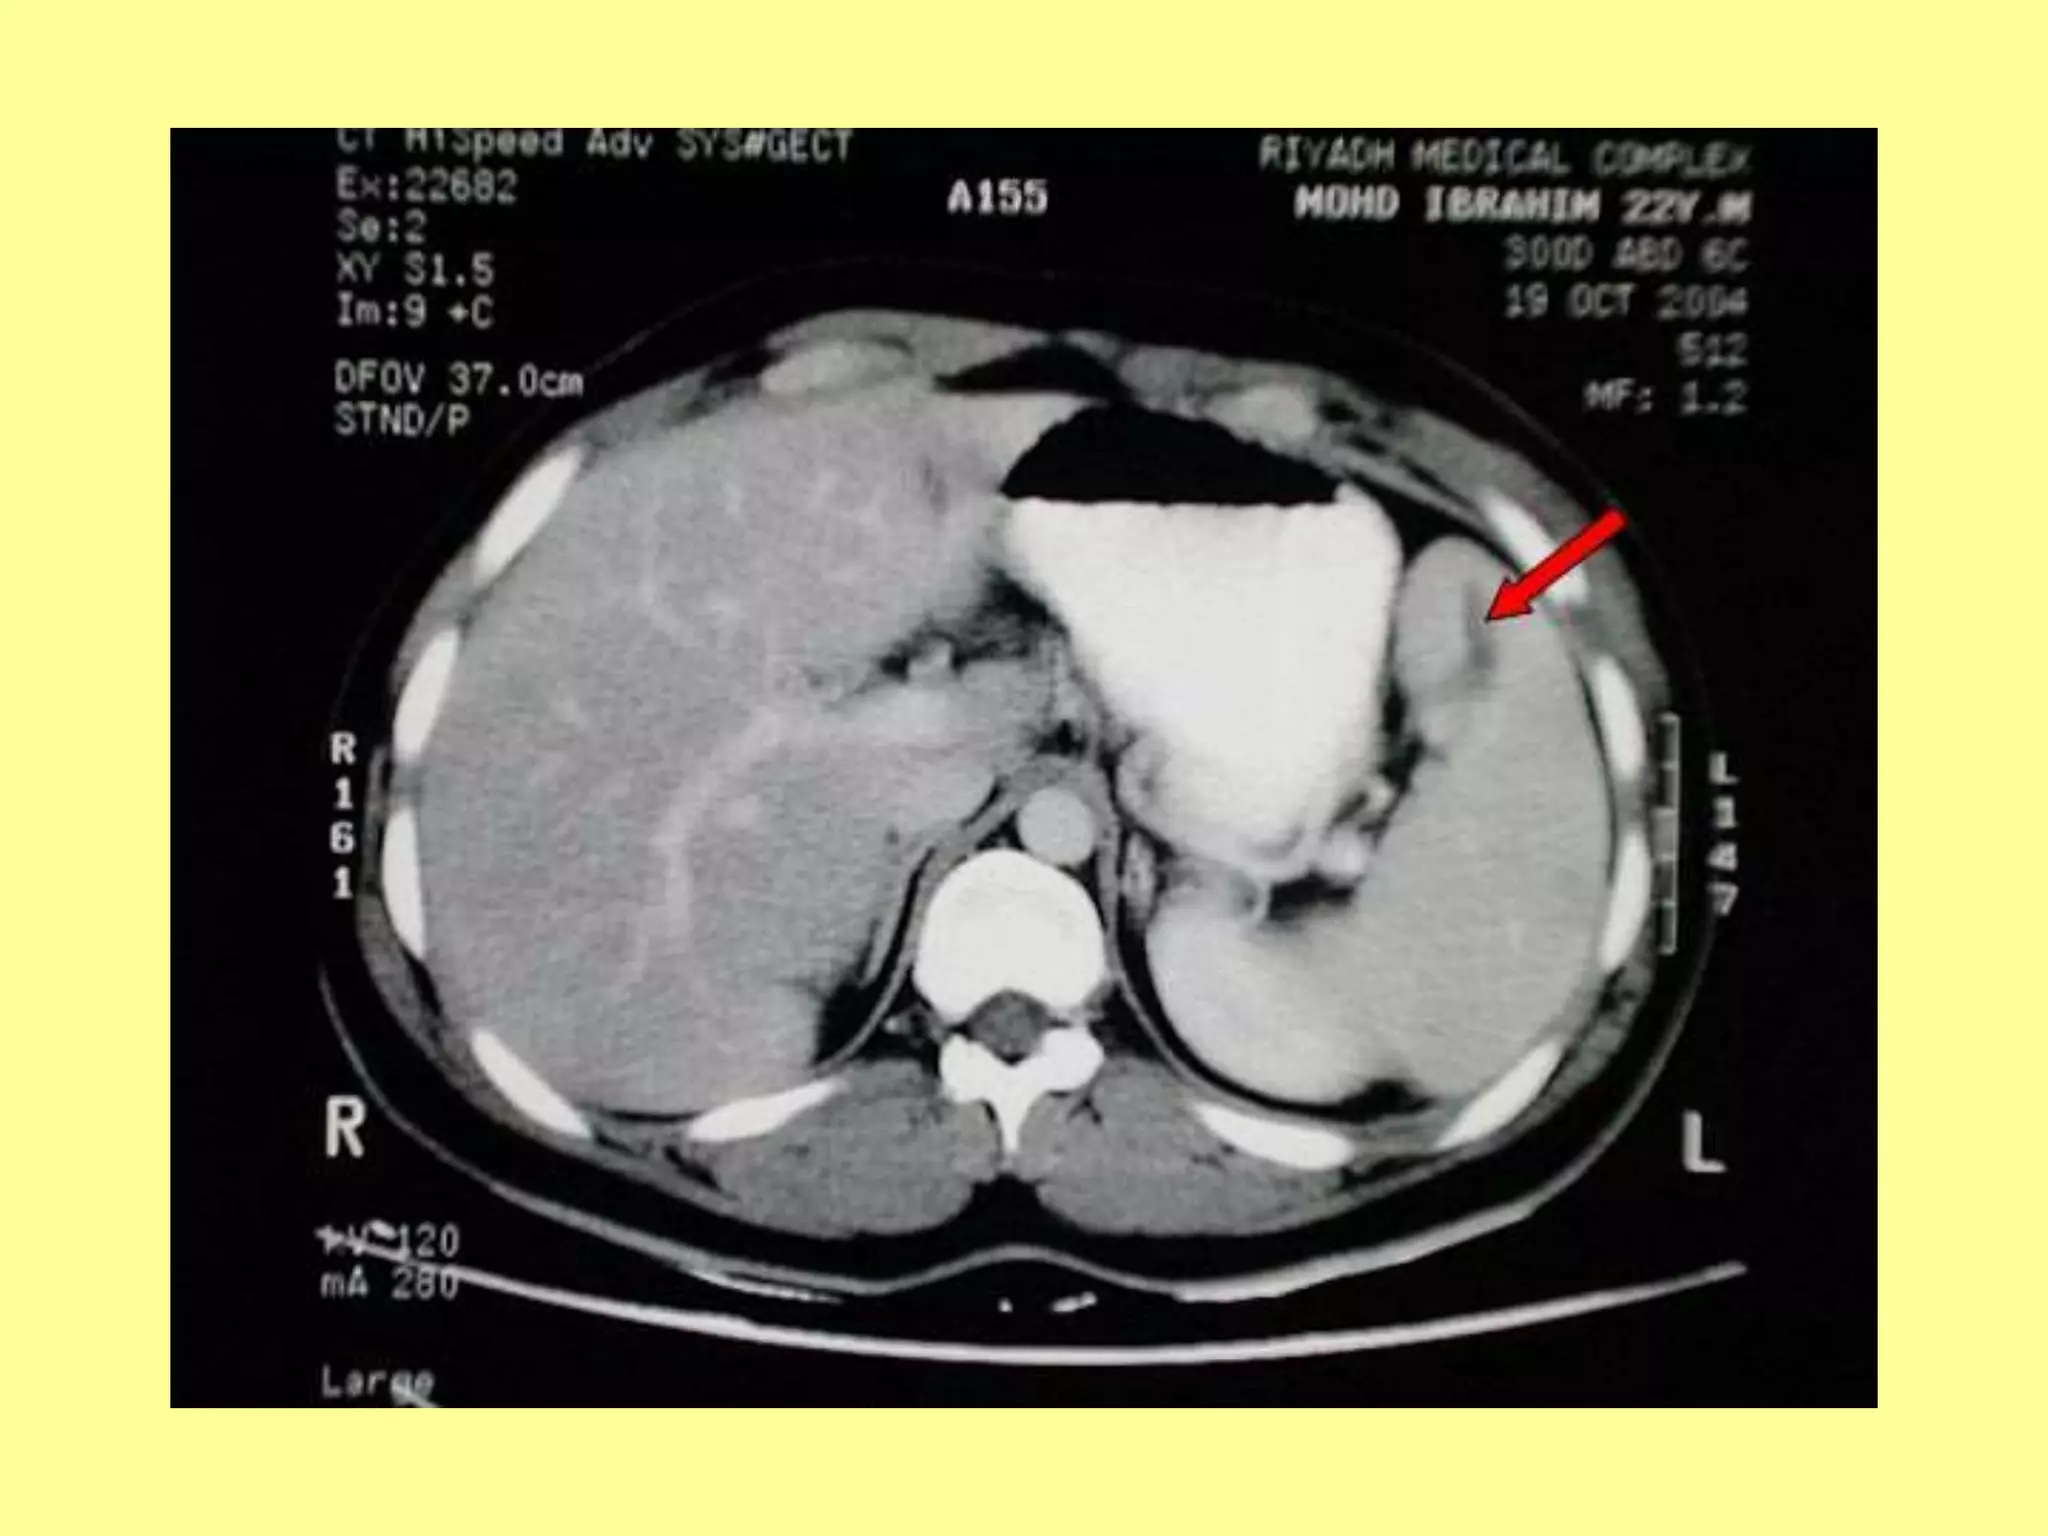

(b) CT.Scan abdomen

used for diagnosing

intraperitoneal injuries in

stable patients after blunt

trauma.

 Non operative approach:

The hepatic injury diagnosed

by CT in stable patient is now

non operative approach

practiced in many centers.